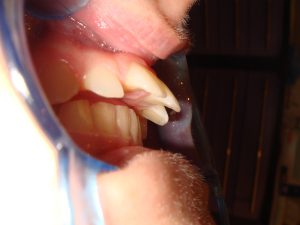

Spaces between teeth can occur in many ways. A patient...